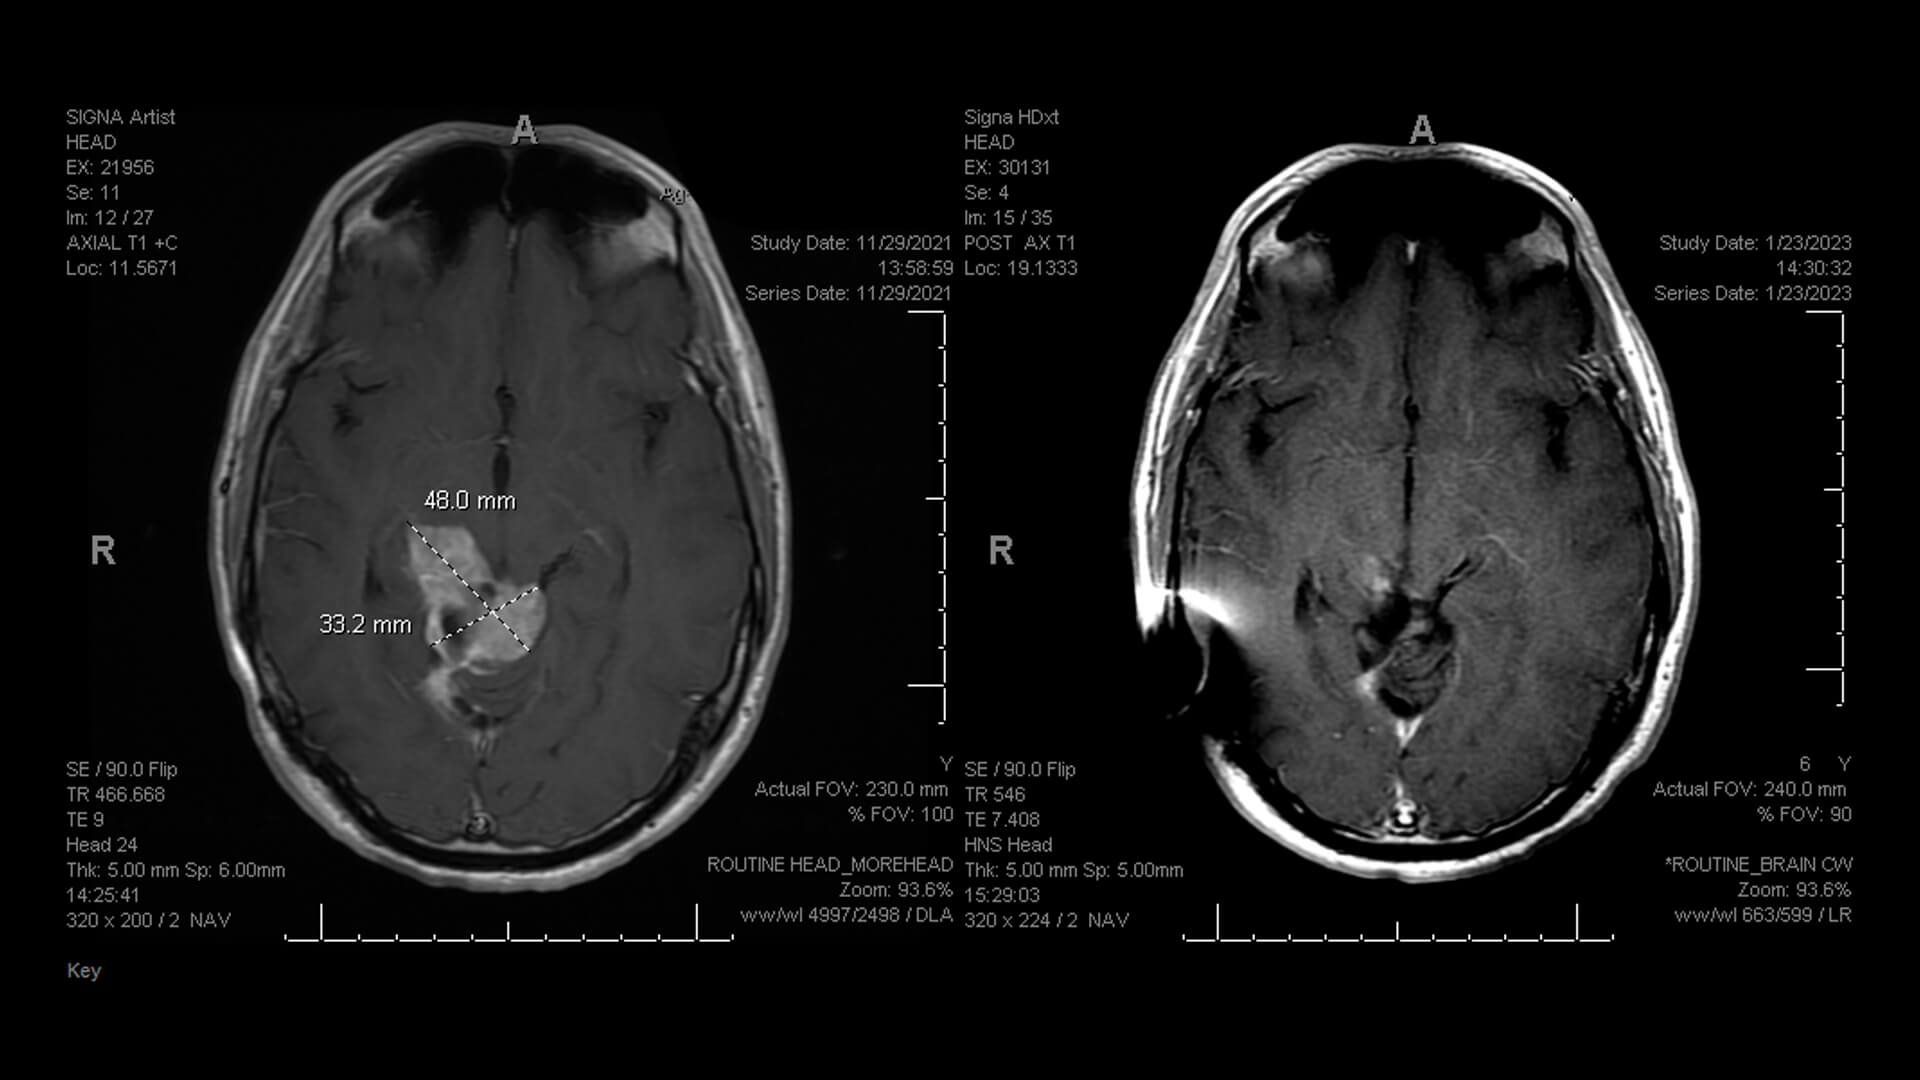

He thought he was having a stroke, so he pulled over and called 911. Emergency teams transported Ethan to Atrium Health Carolinas Medical Center, where he received a CT scan. The scans revealed a complex tumor in Ethan’s brain and upper spinal cord: what would ultimately be shown to be a diffuse cancerous astrocytoma with a rare mutation. As a first step in his care, Ethan would need surgery to remove as much of the lacrosse-ball-sized tumor as possible. He turned to the team of specialized experts at Atrium Health Neurosciences Institute for help.

Nearly two years after Ethan’s initial medical care began, regular scans showed that the tumor had stopped responding to traditional therapies. Instead, the tumor had spread to Ethan’s entire spinal cord. Dr. Sumrall recommended two new targeted therapies that had just become available outside of a clinical trial setting. Ethan started Dabrafenib and Trametinib, medications that help stop tumor growth by blocking different growth-promoting signals in tumor cells.

“The tumor just melted away on the scans,” says Angie.

Within two months, his scans looked significantly better.

“Ethan’s response to new therapies has been extraordinary; it’s now difficult to notice the tumor on his scans,” says Sumrall. “At Levine Cancer, we are committed to finding the latest treatments close to home that give patients the best chance at a longer, healthier life."